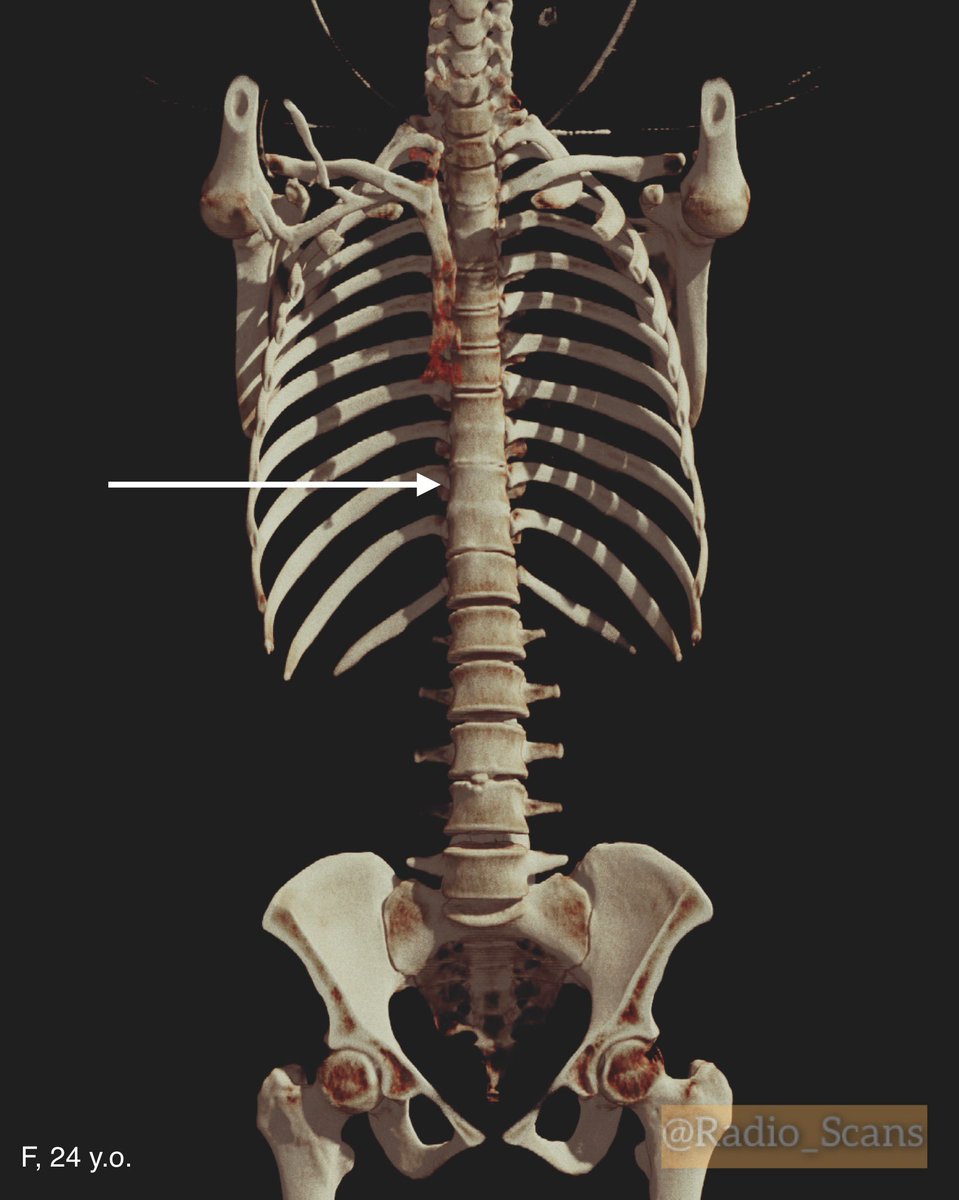

Block vertebrae. CT scans of a 24-year-old female. Notice violation of a failure to separate Th8, Th9, Th10 and Th11 vertebral bodies and blocked vertebrae too. #computed #tomography #ctscan #64slice #blocked #vertebra #failure #separation #vertebral #bodies #anatomic #variant

Radio_Scans's tweet image. Block vertebrae. CT scans of a 24-year-old female. Notice violation of a failure to separate Th8, Th9, Th10 and Th11 vertebral bodies and blocked vertebrae too.